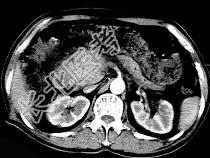

- 单项选择题男,50岁, 黄疸进行性加重、腹部胀痛不适、食欲减退、体重减轻、上腹部可触及肿块,CT如图, 最可能的诊断是 ( )

A、胰头癌

B、转移瘤

C、慢性胰腺炎

D、急性胰腺炎

E、腹膜后淋巴瘤